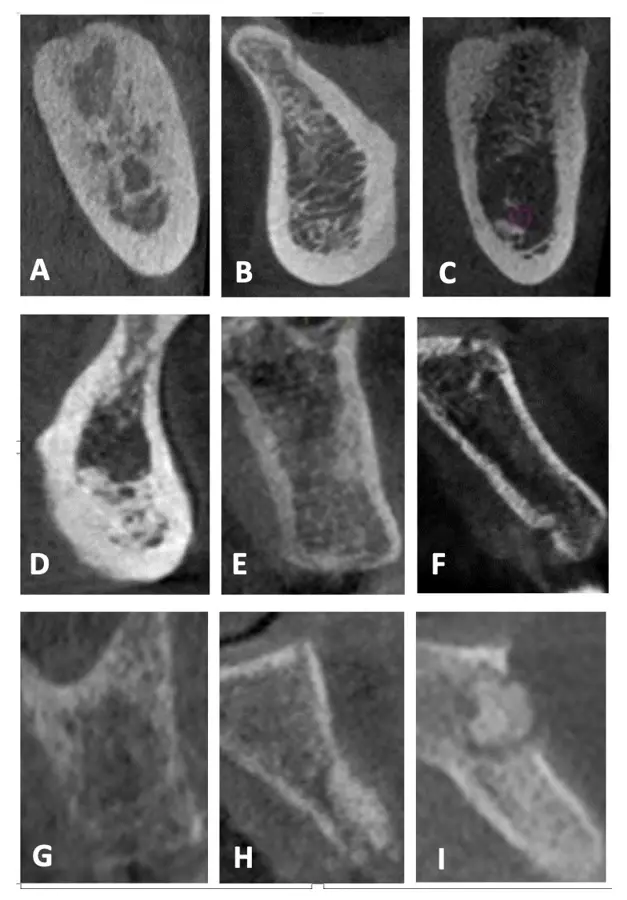

Una reciente publicación de estudios con CBCT propone una modificación a lo anteriormente propuesto por Lekholm y Zarb, que permite sugerir su aplicabilidad para distinguir entre las diversas combinaciones de hueso cortical y esponjoso para definir adecuadamente el tratamiento a fin de optimizar los resultados.17 Esta propuesta se basa en la evaluación de la calidad ósea respecto al grosor de la cortical y a la visibilidad de la cantidad de trabéculas y el tamaño de los espacios medulares en el hueso esponjoso (Figura 4):

• Tipo I: Hueso cortical predominante que rodea al hueso esponjoso de cantidad escasa con trabéculas nítidas en toda la imagen y presencia de espacios medulares pequeños y visibles.

• Tipo II-A: Hueso cortical grueso que rodea al hueso esponjoso de cantidad abundante con trabéculas nítidas en toda la imagen y presencia de espacios medulares pequeños y visibles.

• Tipo II-B: Hueso cortical grueso que rodea al hueso esponjoso de cantidad abundante con predominio de trabéculas difusas en el hueso basal y presencia predominante de espacios medulares amplios y visibles.

• Tipo II-C: Hueso cortical grueso que rodea al hueso esponjoso de cantidad abundante con predominio de trabéculas muy gruesas y nítidas en la basal, con presencia de espacios medulares pequeños y visibles.

• Tipo III-A: Hueso cortical delgado que rodea al hueso esponjoso de cantidad abundante con trabéculas nítidas en toda la imagen y presencia de espacios medulares pequeños y visibles.

• Tipo III-B: Hueso cortical delgado que rodea al hueso esponjoso de cantidad abundante con predominio de trabéculas difusas y presencia de espacios medulares difusos.

• Tipo IV: Hueso cortical difuso que rodea al hueso esponjoso de cantidad abundante con predominio de trabéculas difusas y presencia de espacios medulares difusos.

• Tipo V: Hueso regenerado, de cantidad, visibilidad de las trabéculas y espacios medulares variables.

• Tipo VI: Hueso con patología, de cantidad, visibilidad de las trabéculas y espacios medulares variables.

Figura 4. Calidad ósea según la clasificación de Lekholm y Zarb modificada. A: Tipo I, B: Tipo II-A, C: Tipo II-B, D: Tipo II-C, E: Tipo III-A, F: Tipo III-B, G: Tipo IV, H: Tipo V, I: Tipo VI.